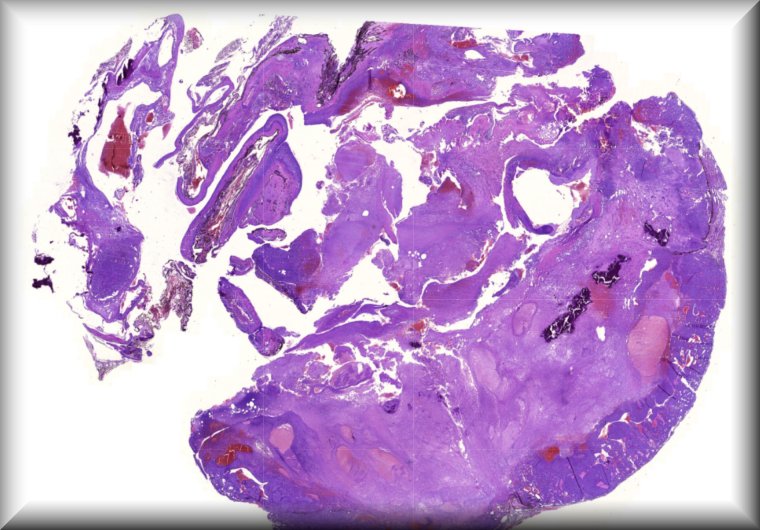

Susan Kennedy: Exenteration specimen of a 70-year-old female who underwent multiple (14) surgeries for conjunctival melanoma over a period of two years. |